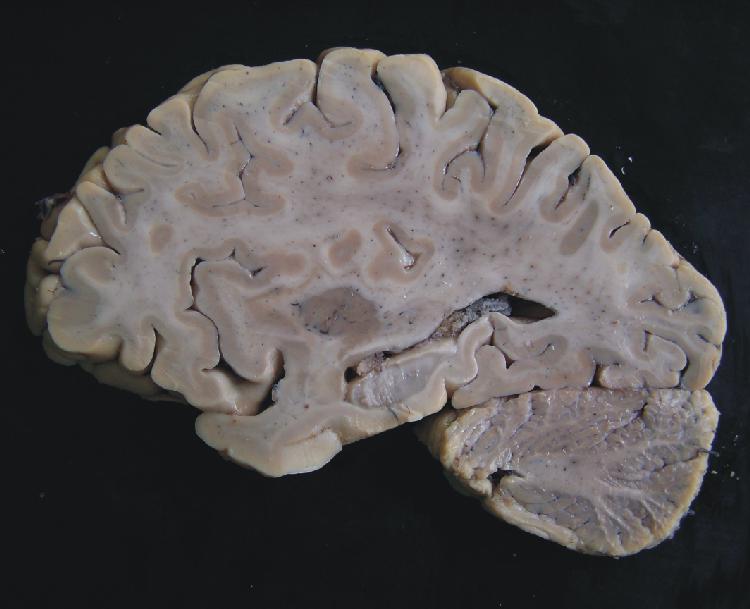

| Sulcus centralis |

| Insula |

| Claustrum |

| Corpus amygdaloideum |

| Putamen |

| Hippocampus |

| Ventriculus lateralis - cornu temporale |

| Ventriculus lateralis - cornu occipitale |

| Ventriculus lateralis - plexus choroideus |

| Cerebellum |

| Fissura prima |

| Fissura horizontalis |